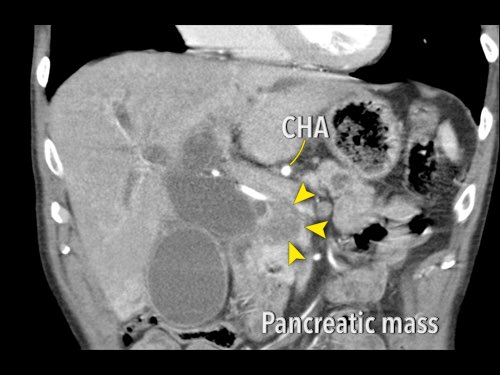

Tái tạo mặt phẳng coronal cho thấy một khối u lớn xuất phát từ cổ tụy với kiểu phát triển xâm lấn (hình A và B).

Có hiện tượng bao quanh động mạch thân tạng 360º (mũi tên trong A).

CT axial MIP tại mức động mạch thân tạng cho thấy hẹp động mạch gan chung bị bao quanh (mũi tên), rất nghi ngờ xâm lấn.